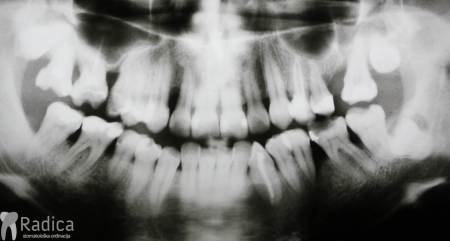

U dolje prikazanim slikama se vidi impaktirani drugi trajni premolar koji je resorbirao dio korijena i krune prvog trajnog molara. Pacijent se javio zbog jakih bolova u području molara koji je bio intaktan te je napravljen ortopantomogram. Molar se morao izvaditi i pacijent je trenutno u terapiji.